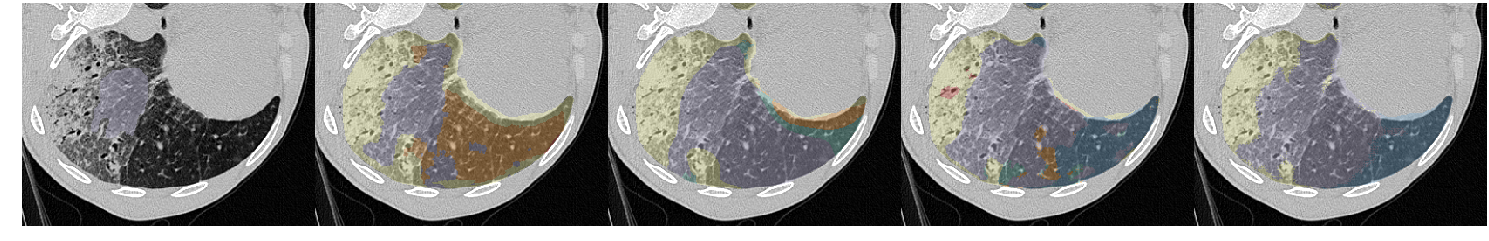

Table III presents a comparison between the proposed network and three previous studies. It has to be noted that all models used the same unsupervised weight (wu=0.1subscript𝑤𝑢0.1w_{u}=0.1) and whenever batch normalization was performed, this was based on batch statistics (instance normalization) since this yielded the best results. Fig. 7 illustrates a few segmentation results for each of the models in Table III.

The first line of the table refers to our previous work [5], which has been converted into a fully convolutional network so it can accept arbitrarily sized images for input. Its low accuracy is probably due to the small receptive field (33×\times33) and the extensive pooling. This architecture was sufficient to describe the local texture of the 32×\times32 single-class patches in [5], but could not capture higher level structure that is present in the whole-lung dataset of this study. The results of the model in Fig. 7 show its noisy output near the lung boundaries or between patterns, where context information could be useful. Segnet [15] and U-net [17] yielded better results, with the latter being slightly faster and substantially more accurate. Both models have a very high number of parameters and large enough receptive fields to capture any relevant information. The superior performance of U-net could be attributed to its skip connections that allow features from the lower scales to directly contribute to its output. Indeed, Fig. 7 illustrates the more detailed results of U-net as opposed to the overly smoothed areas produced by Segnet. Finally, the proposed network yielded the best results, while being faster and having far fewer parameters. The output examples in Fig. 7 indicate that the proposed model manages to keep a better balance between fine details and smooth border among the different classes. Even thought it is really difficult to visually assess the performance of the system for the different classes, there are a few examples in Fig. 7 with wrong classifications on which we can comment. Firstly, parts of the broncho-vascular tree in the third row were recognized as consolidation because of their similar densities, while accentuated terminal bronchial parts, that might be physiological as well, caused the erroneous classification of healthy areas into reticulation, in the first row. Some mistakes however are also attributed in the limited number of annotated classes. For example in row 6, there are emphysematic areas (dark area in the center of the lung) that have been annotated as healthy due to their similar density. Figure 6 shows the confusion matrix of the proposed model. As expected, many of the misclassifications occur between reticulation and honeycombing due to their similar textural appearance. Moreover, healthy tissue is often confused with reticulation probably because of the 2D sections of the bronchovascular tree that could resemble reticular patterns.

Refer to caption

Figure 7: Output examples for the models of Table III. From left to right: Ground Truth, ILD-CNN, Segnet, U-net, Proposed. Each example has a different pattern annotated. From top to bottom: Healthy (Blue), Ground Glass Opacity (Purple), Micronodules (Green), Consolidation (Yellow), Reticulation (Orange) and Honeycombing (Red).